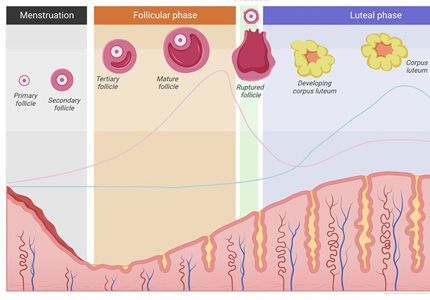

המחזור החודשי

צלילה אל המנגנון ההורמונלי המרתק שמנהל את גוף האישה מדי חודש. נלמד להבין את השלבים השונים של המחזור, ההורמונים המשתתפים בתהליך והשפעתם על הגוף.